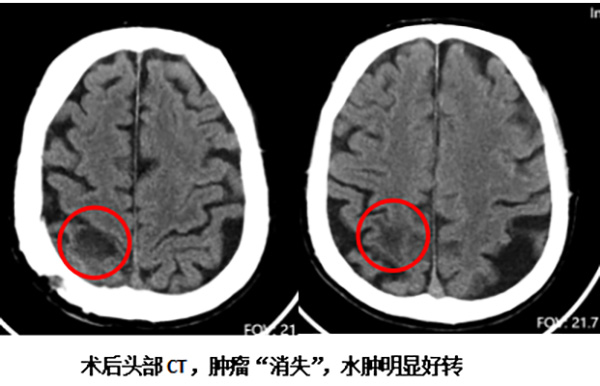

决策既定,手术团队制定了周详的手术计划。手术过程中,在术中超声辅助定位下,寻找到了中央后回受累最严重的狭小区域,经过最小化损伤通道,成功将位于功能区的肿瘤完整切除,并最大限度地保护了周边正常的神经组织。

手术效果立竿见影。术后,老人左侧肢体的肌力得到了明显改善,之前下床费力的症状基本完全缓解。这一成功的手术,不仅解决了最迫切的神经功能问题,极大地提升了患者的生存质量,也实现了团队的初步战略目标——为后续治疗打开了局面。